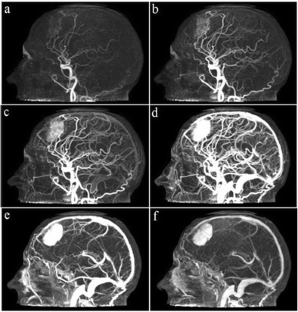

Fig. 3